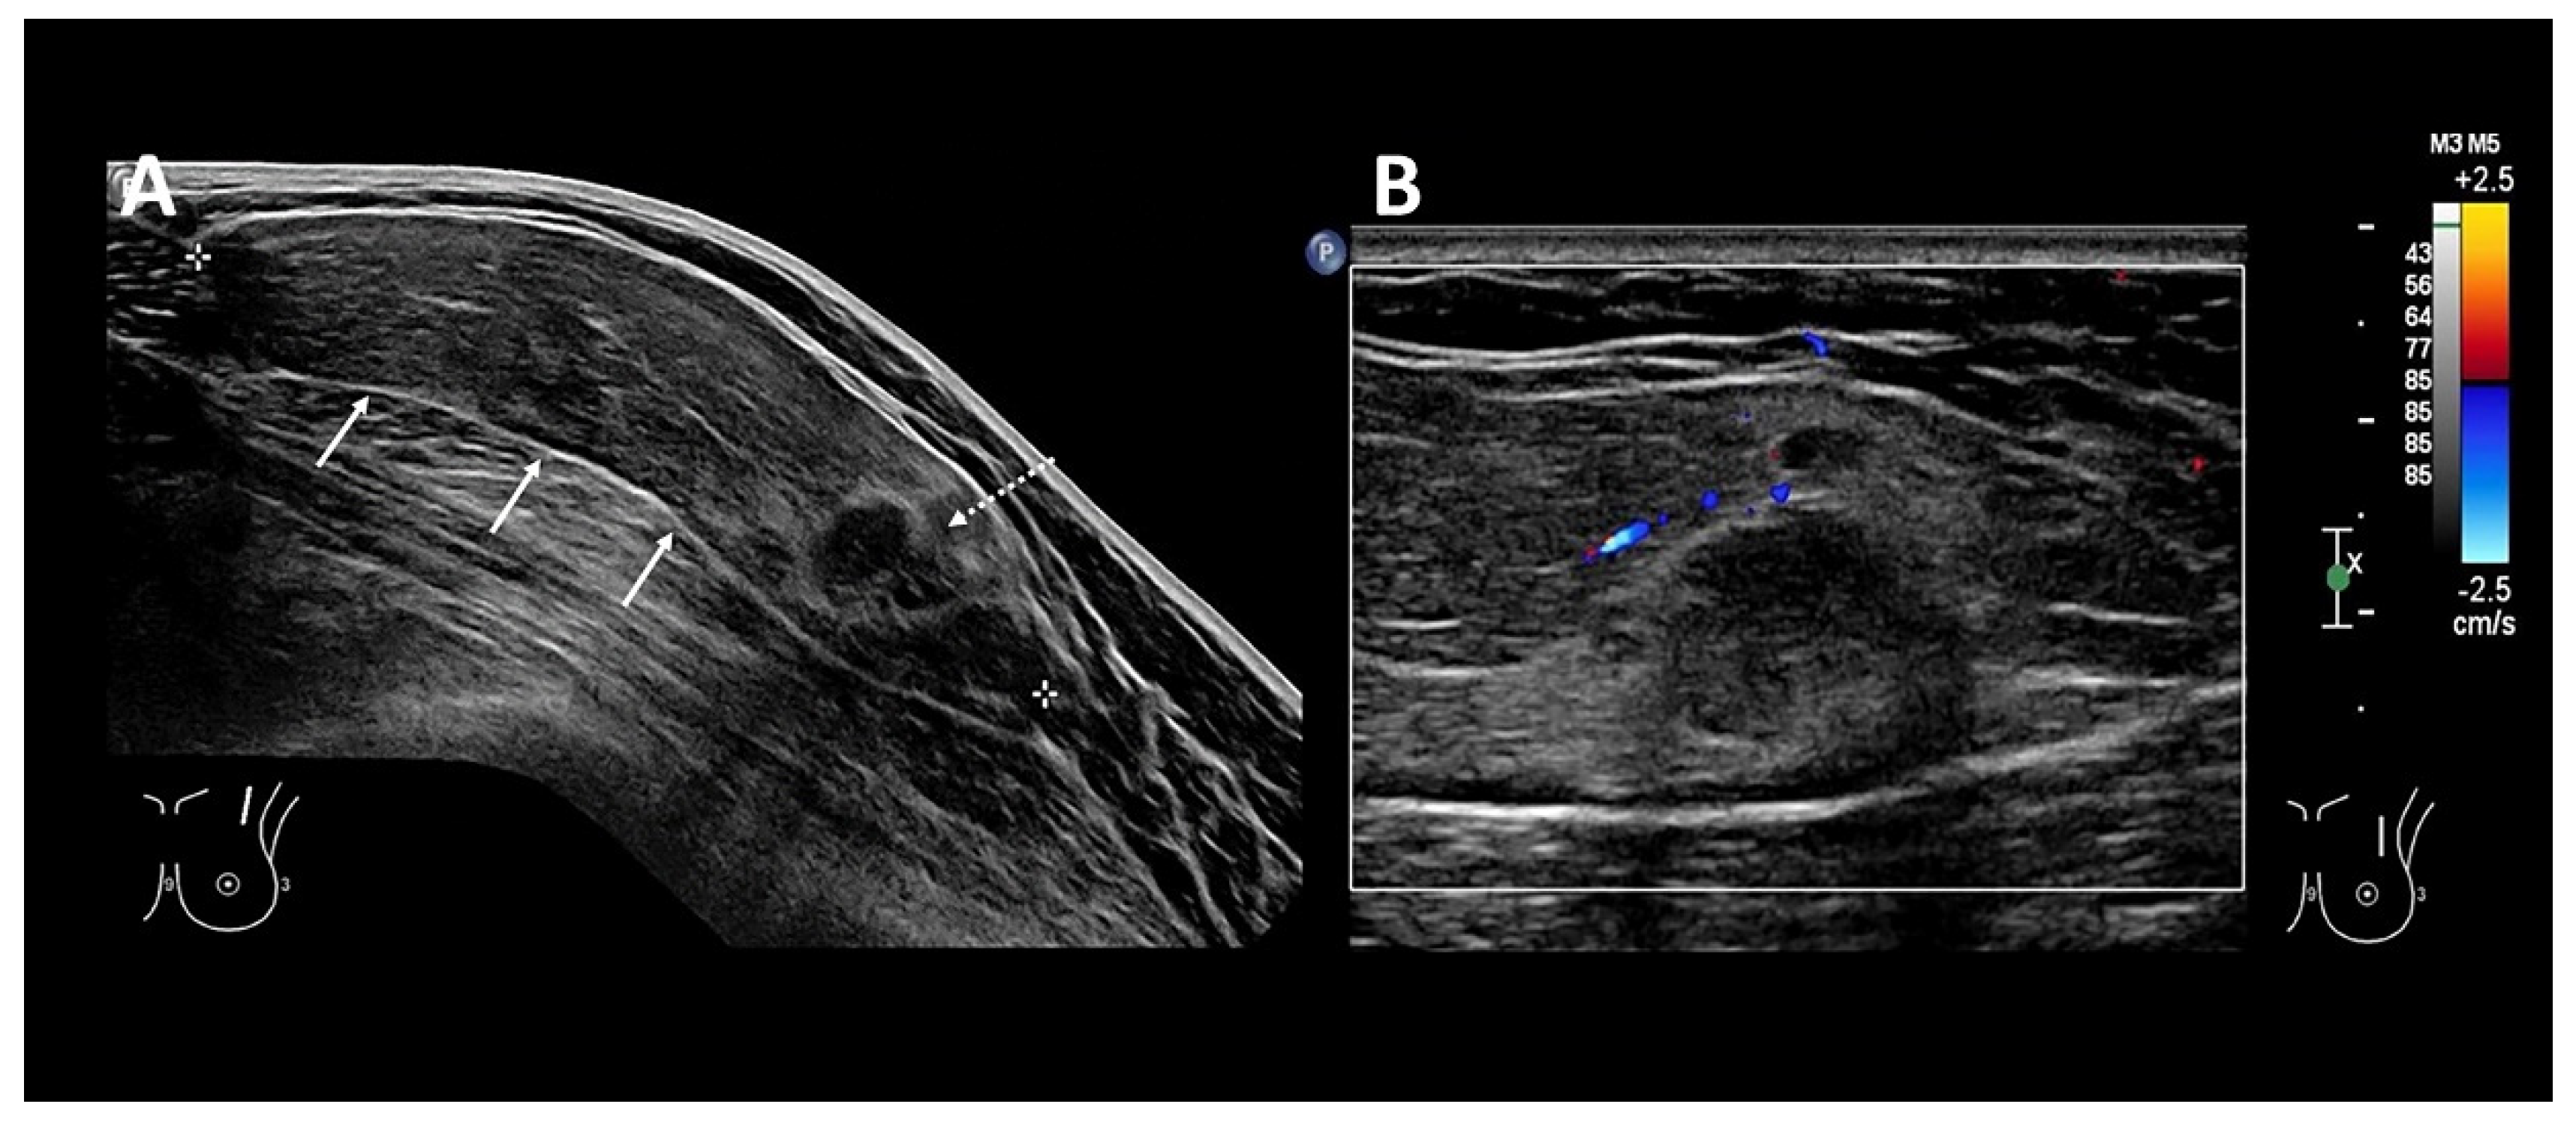

- Goh, Y.; Balasundaram, G.; Tan, H.M.; Putti, T.C.; Tang, S.W.; Ng, C.W.Q.; Buhari, S.A.; Fang, E.; Moothanchery, M.; Bi, R.; et al. Biochemical “decoding” of breast ultrasound images with optoacoustic tomography fusion: First-in-human display of lipid and collagen signals on breast ultrasound. Photoacoustics 2022, 27, 100377. [Google Scholar] [CrossRef]